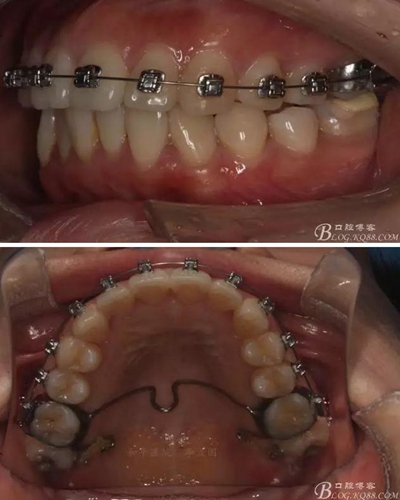

患者,女,主訴:牙齒不齊。

如圖,該病例為簡(jiǎn)單排齊病例,但77鎖合是矯治中的關(guān)鍵所在,你會(huì)怎么處理?

該病例主要為17、27頰側(cè)位同時(shí)伴有伸長(zhǎng),當(dāng)然種植支抗可以解決,但還有簡(jiǎn)單實(shí)用的辦法嗎?如圖,在橫腭桿遠(yuǎn)中延伸出牽引鉤,位置盡量遠(yuǎn)離合平面,7粘舌側(cè)扣,牽引力的方向?yàn)閴旱图吧嘞?,下圖為兩個(gè)月的效果,17已到位,27還未到位。